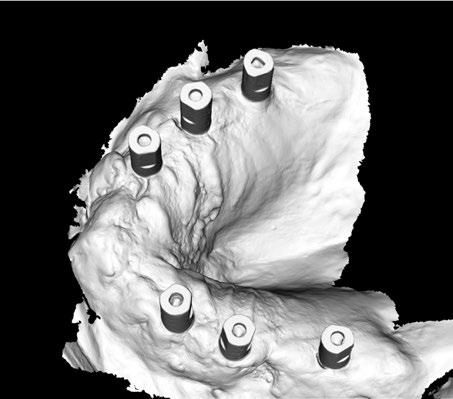

A tenor del estado oral proponemos múltiples opciones terapéuticas, consensuando entre paciente y facultativos una rehabilitación implantoprotésica fija superior e inferior. Debido a la lejanía de la residencia de la paciente, y motivados por las necesidades estéticas que esta exige, consideramos realizar una carga inmediata impresa con resina definitiva el mismo día de la cirugía. Tras el escaneado intraoral con el escáner Dexis IS3700 (Figuras 7 y 8) y realización de CBCT, subimos los ficheros a la plataforma Bego Guide,

procediendo a realizar una solicitud de encargo a través de un formulario. Antes de 72 horas recibimos una propuesta terapéutica. En ella se facilitan vistas 3D detalladas, así como valoraciones y consideraciones a tener en cuenta durante el fresado y la inserción de los implantes (Figuras 9 a 19). Decidimos realizar extracción de todas las piezas remanentes, dada su nula viabilidad a corto-medio plazo y en Bego (a través del portal) proponen mantener 3 piezas (las más viables técnicamente) en cada arcada para proporcionar el anclaje óptimo de la

férula. Tras la aceptación del caso envían a la clínica la férula quirúrgica junto con un claro protocolo de secuencia de fresado.

Ejecución técnica quirúrgica mediante férula guiada Bajo anestesia infiltrativa realizamos extracciones atraumáticas de todas las piezas a excepción de los dientes que actúan como anclaje o pilares para la fijación de la férula quirúrgica (Figuras 20 y 21). Seguidamente insertamos la férula comprobando una buena adaptabilidad y estabilidad

(Figuras 22 y 23). Se realiza fresado transgingival mínimamente invasivo y guiado hasta la inserción de los implantes, siguiendo el protocolo preestablecido e indicado (Figuras 24 a 26).

Durante la colocación de los implantes comprobamos una inserción con torque superior a 35 N/cm2

Retiramos la férula y comprobamos una correcta estabilidad primaria mediante mediación de valores

ISQ favorables en la mayoría de los implantes. Seguidamente se extraen los dientes remanentes que han actuado de medio retentivo para la férula quirúrgica.

Dentro de la fase quirúrgica propiamente dicha, una vez terminada la inserción de los implantes y

comprobada su estabilidad primaria, colocamos pilares transepiteliales

Multiplus para registrar una impresión digital mediante escaneado sobre ellos (Figuras 27 a 29)